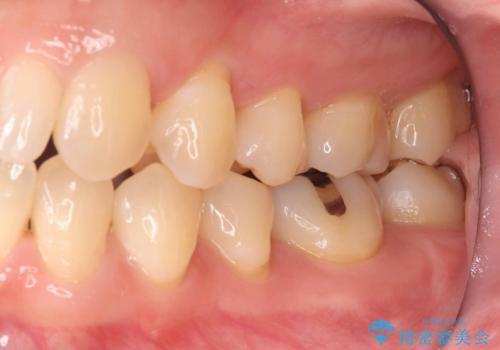

歯が欠けたことによるものか、もしくは以前装着された修復物の不適合が原因と考えられますが、銀歯(メタルインレー)と歯との間に大きな段差が認められ、汚れが溜まりやすい状態となっていました。

このような状態では、修復物の内部で虫歯が進行している可能性が高いため、治療が必要と判断しました。